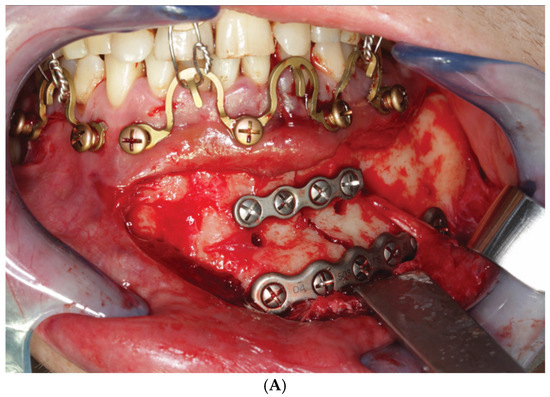

3.3. ‘In-Situ-Bending’ for Fracture Reduction